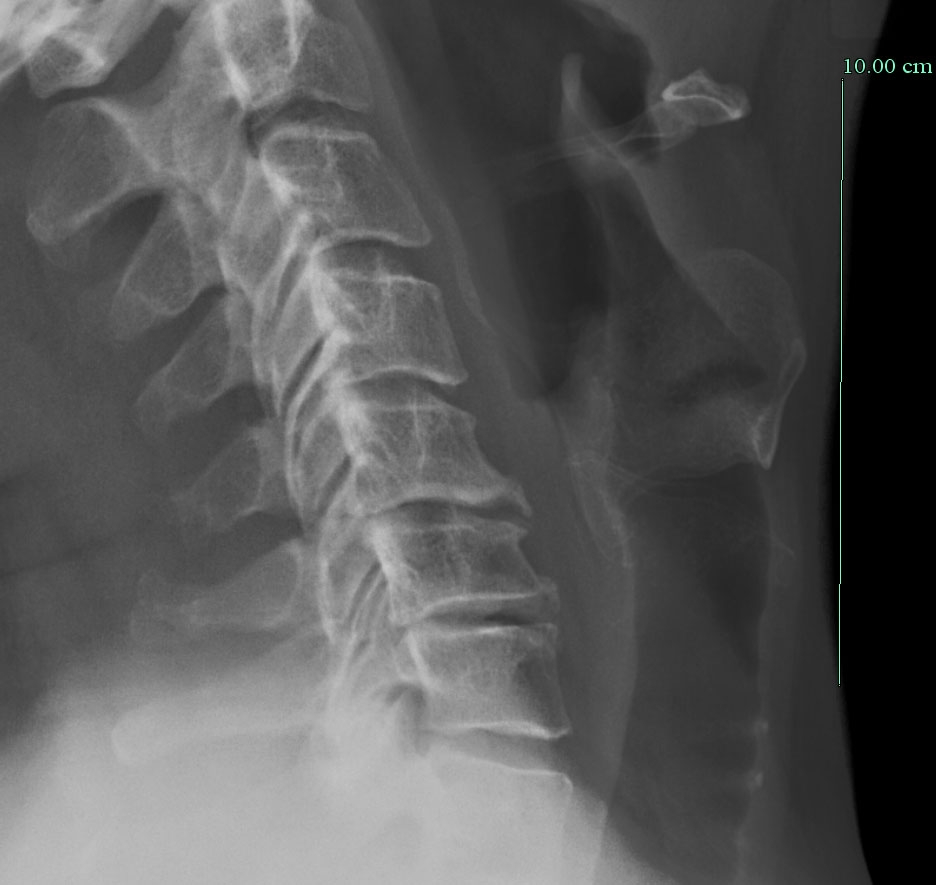

back_large.jpg preview

A conventional X-ray taken before surgery. Note the rather sinister "hook" on the front of the affected joints, where the bone is growing over the extruded discs (not visible in this X-ray). This is happening on the back side, which has to be removed. Getting rid of all that crunchy bone without harming the spinal cord is why neurosurgeons get paid a lot.

Contrast this X-ray with the next ones, where you can see the new artificial joints.